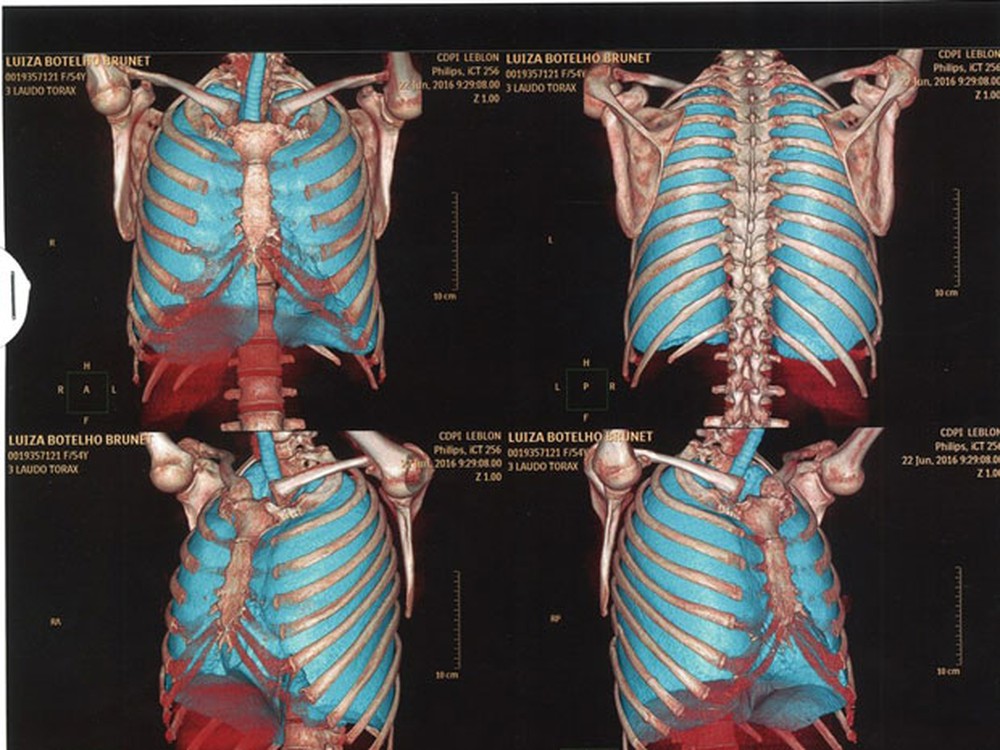

Laudo e imagens de tomografia mostram fraturas em 4 costelas de Luiza Brunet

Um laudo e imagens de tomografia computadorizada, de junho de 2016, mostram que Luiza Brunet teve quatro costelas fraturadas. A atriz e modelo de 54 anos acusa o ex-companheiro, o empresário Lírio Parisotto, de 62, de quebrar suas costelas em 21 de maio de 2016 durante uma briga nos Estados Unidos.

Segundo o laudo, foi constatada “fratura sem desvio significativo, da porção ântero-lateral do 7º ao 10º arcos costais à direita, com formações de calos ósseos incipientes”. O laudo e as imagens das fraturas estão no processo, que é digitalizado.

Laudo informa que imagens de tomografia detectaria fraturas em quatro costelas de Luiza Brunet (Foto: Reprodução)